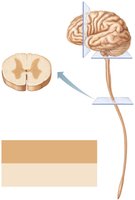

Organization of Gray and White Matter

Distribution Patterns

The CNS displays characteristic patterns of gray matter (neuron cell bodies, dendrites, glial cells) and white matter (myelinated axons):

In the spinal cord: central gray matter surrounded by white matter.

In the brain stem: additional gray matter nuclei embedded within white matter.

In the cerebrum and cerebellum: outer cortex of gray matter, inner white matter, and deep gray matter nuclei.